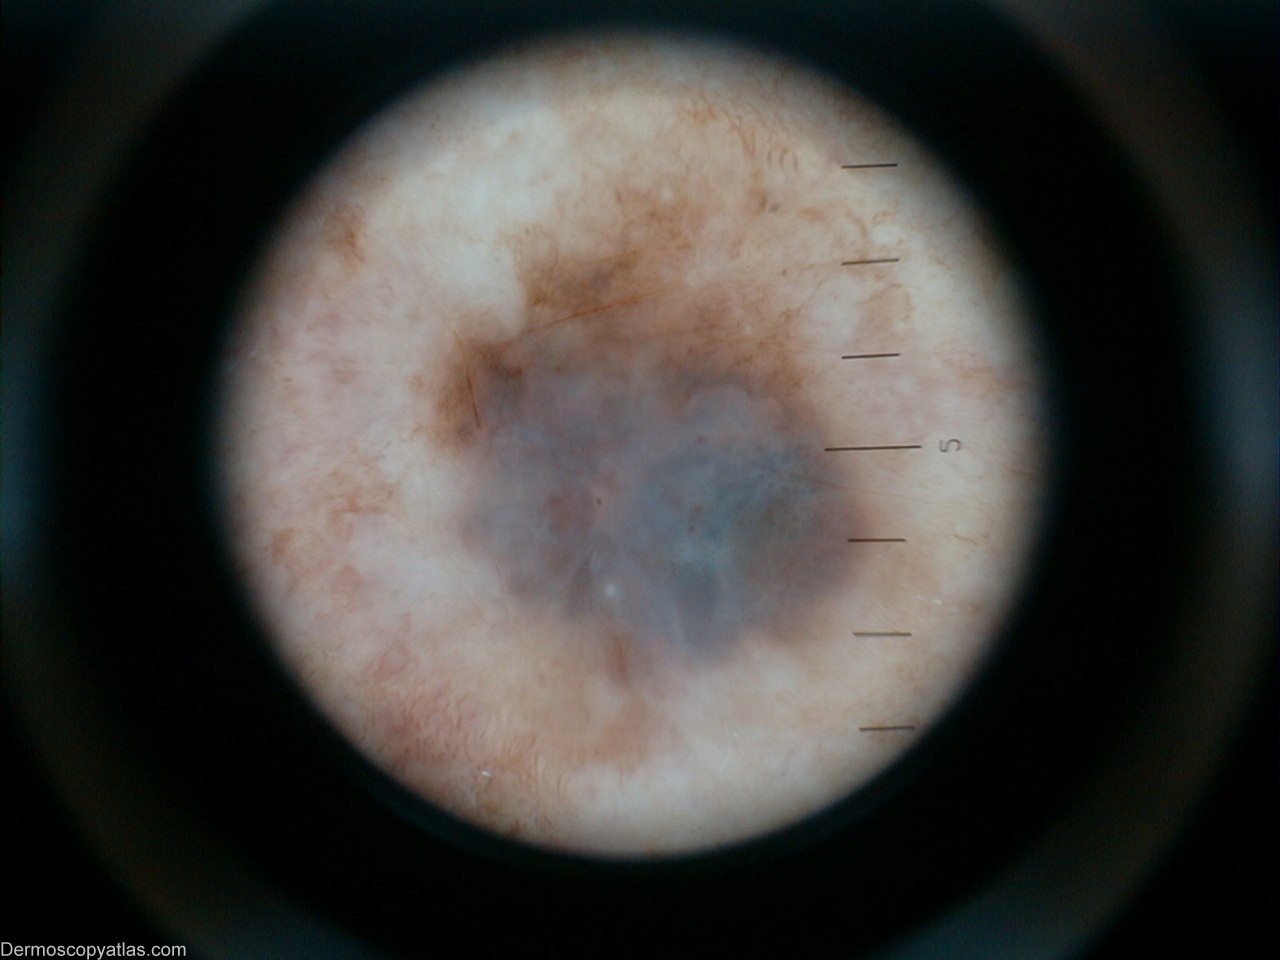

Diagnosis: Melanoma invasive

View